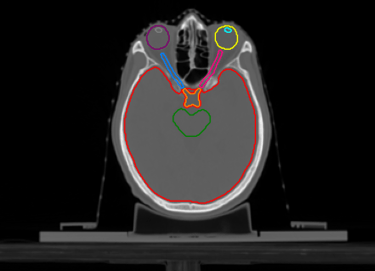

O SegmentaR foca na segmentação automática das três regiões fundamentais para o planejamento de radioterapia: cabeça e pescoço, tórax e pelve. Essas são as regiões essenciais que todo profissional precisa para uma segmentação precisa e eficiente.

Cabeça e Pescoço

Mandíbula

Cérebro

Tronco Cerebral

Cavidade Oral

Cóclea Esquerda

Cóclea Direita

Esôfago

Olho Direito

Olho Esquerdo

Glândula Tireoide

Laringe

Cristalino Direito

Cristalino Esquerdo

Quiasma Óptico

Nervo Óptico Esquerdo

Nervo Óptico Direito

Parótida Esquerda

Parótida Direita

Medula Espinhal